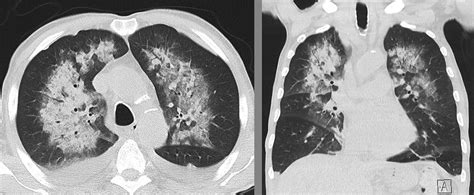

• Imaging Tests: Chest X-rays and CT scans can help visualize the lungs and identify areas of bleeding.

• diffuse alveolar hemorrhage radiology